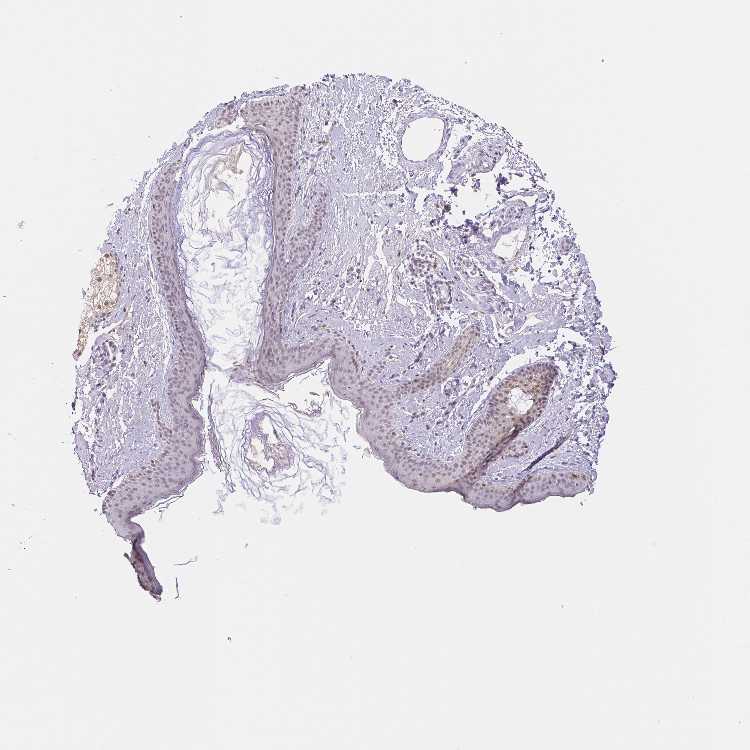

SKIN 1 - Antibody stainingi

Antibody staining in the annotated cell types in the current human tissue is reported as not detected, low, medium, or high, based on conventional immunohistochemistry profiling in selected tissues. This score is based on the combination of the staining intensity and fraction of stained cells.

Each image is clickable and will lead to virtual microscopy that enables deeper exploration of all samples and also displays staining intensity scores, fraction scores and subcellular localization as well as patient and tissue information for each sample.

Antibody HPA064194

Langerhans Not detected

Fibroblasts Not detected

Keratinocytes Not detected

Melanocytes Not detected

SKIN 2 - Antibody stainingi

Epidermal cells Low